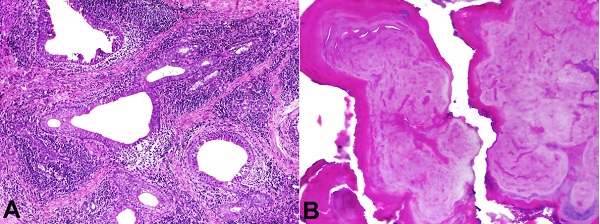

The microscopic examination revealed a fibrovascular stroma containing foci of neutrophil infiltration, acinar atrophy, and numerous dilated salivary gland ducts surrounded by an abundant chronic inflammatory infiltrate (Figure 3A). The hard tissue showed basophilic calcified material with a fingerprint-like appearance in a concentric pattern (Figure 3B). The histopathological features and presence of sialoliths led to a final diagnosis of SMSG. After a 3-year follow-up, the patient had a stable condition, without recurrence or alteration in the lesion area.